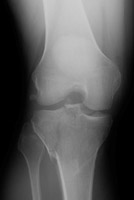

- Click on the image for a larger versionCAP radiograph of the knee. The fractures of the medial and lateral aspects of the tibial plateau are now easily visible.